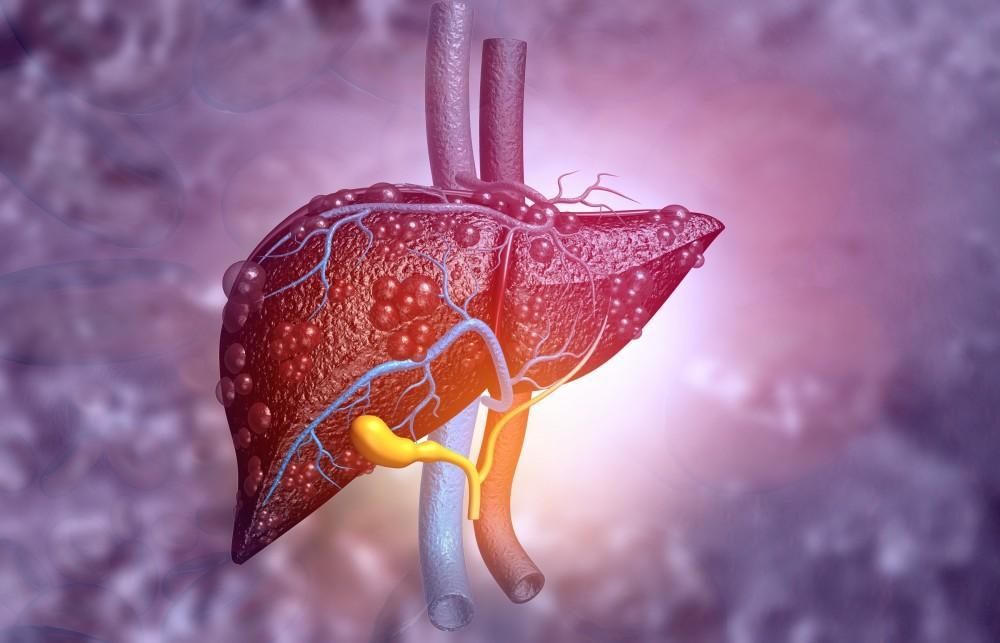

Bis zu einem von vier Erwachsenen weltweit ist von einer nichtalkoholischen Fettlebererkrankung betroffen (Abbildung von Medical Xpress)

Bisher wurde die Fettlebererkrankung einschließlich NAFLD mit einem erhöhten Risiko für Leberzirrhose, Leberkrebs, Lebertransplantationen und Stoffwechselerkrankungen wie Diabetes in Verbindung gebracht.

„Die Leber spielt eine wichtige Rolle im menschlichen Immunsystem, wobei Immunzellen wie Makrophagen und Lymphozyten bis zu 20 % aller Leberzellen ausmachen“, erklärt Dr. Ebrahimi.

Der Rückgang der Leberfunktion führt zu einem Rückgang der vorhandenen Immunzellen und damit zu einer höheren Anfälligkeit für Infektionen durch Viren, Bakterien, Pilze usw.; bei schweren Infektionen (die einen Krankenhausaufenthalt erfordern) und medikamentenresistenten Infektionen besteht ein hohes Sterberisiko.

Nach 20 Jahren Leben mit NALFD besteht bei jedem sechsten Patienten das Risiko einer schweren Infektion.

Die neuen Erkenntnisse unterstreichen die Bedeutung der Diagnose und Behandlung von NALFD in allen Stadien. Laut Statistik betrifft diese Krankheit weltweit bis zu einem Viertel aller Erwachsenen. Zu den Risikogruppen für NALFD zählen Menschen mit Adipositas, Typ-2-Diabetes, Dyslipidämie, metabolischem Syndrom, polyzystischem Ovarialsyndrom, Schilddrüsenunterfunktion usw.